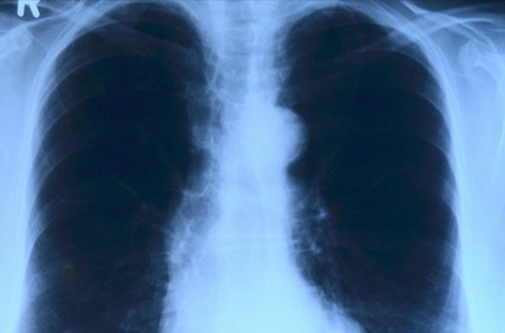

TB CHEST DS

Pulmonology is a medical speciality that deals with diseases involving the respiratory tract. The term is derived from the Latin word pulmō, pulmōnis ("lung") and the Greek suffix -λογία, -logia ("study of"). Pulmonology is synonymous with pneumology (from Greekπνεύμων ("lung") and -λογία), respirology and respiratory medicine. Pulmonology is known as chest medicine and respiratory medicine in some countries and areas. Pulmonology is considered a branch of internal medicine, and is related to intensive care medicine. Pulmonology often involves managing patients who need life support and mechanical ventilation. Pulmonologists are specially trained in diseases and conditions of the chest, particularly pneumonia, asthma, tuberculosis, emphysema, and complicated chest infections.